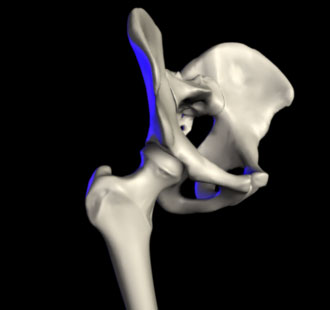

In anatomy, the hip is the bony projection of the femur which is known as the greater trochanter, and the overlying muscle and fat. The hip joint, scientifically referred to as the acetabulofemoral joint, is the joint between the femur and acetabulum of the pelvis and its primary function is to support the weight of the body in both static (e.g. standing) and dynamic (e.g. walking or running) postures.